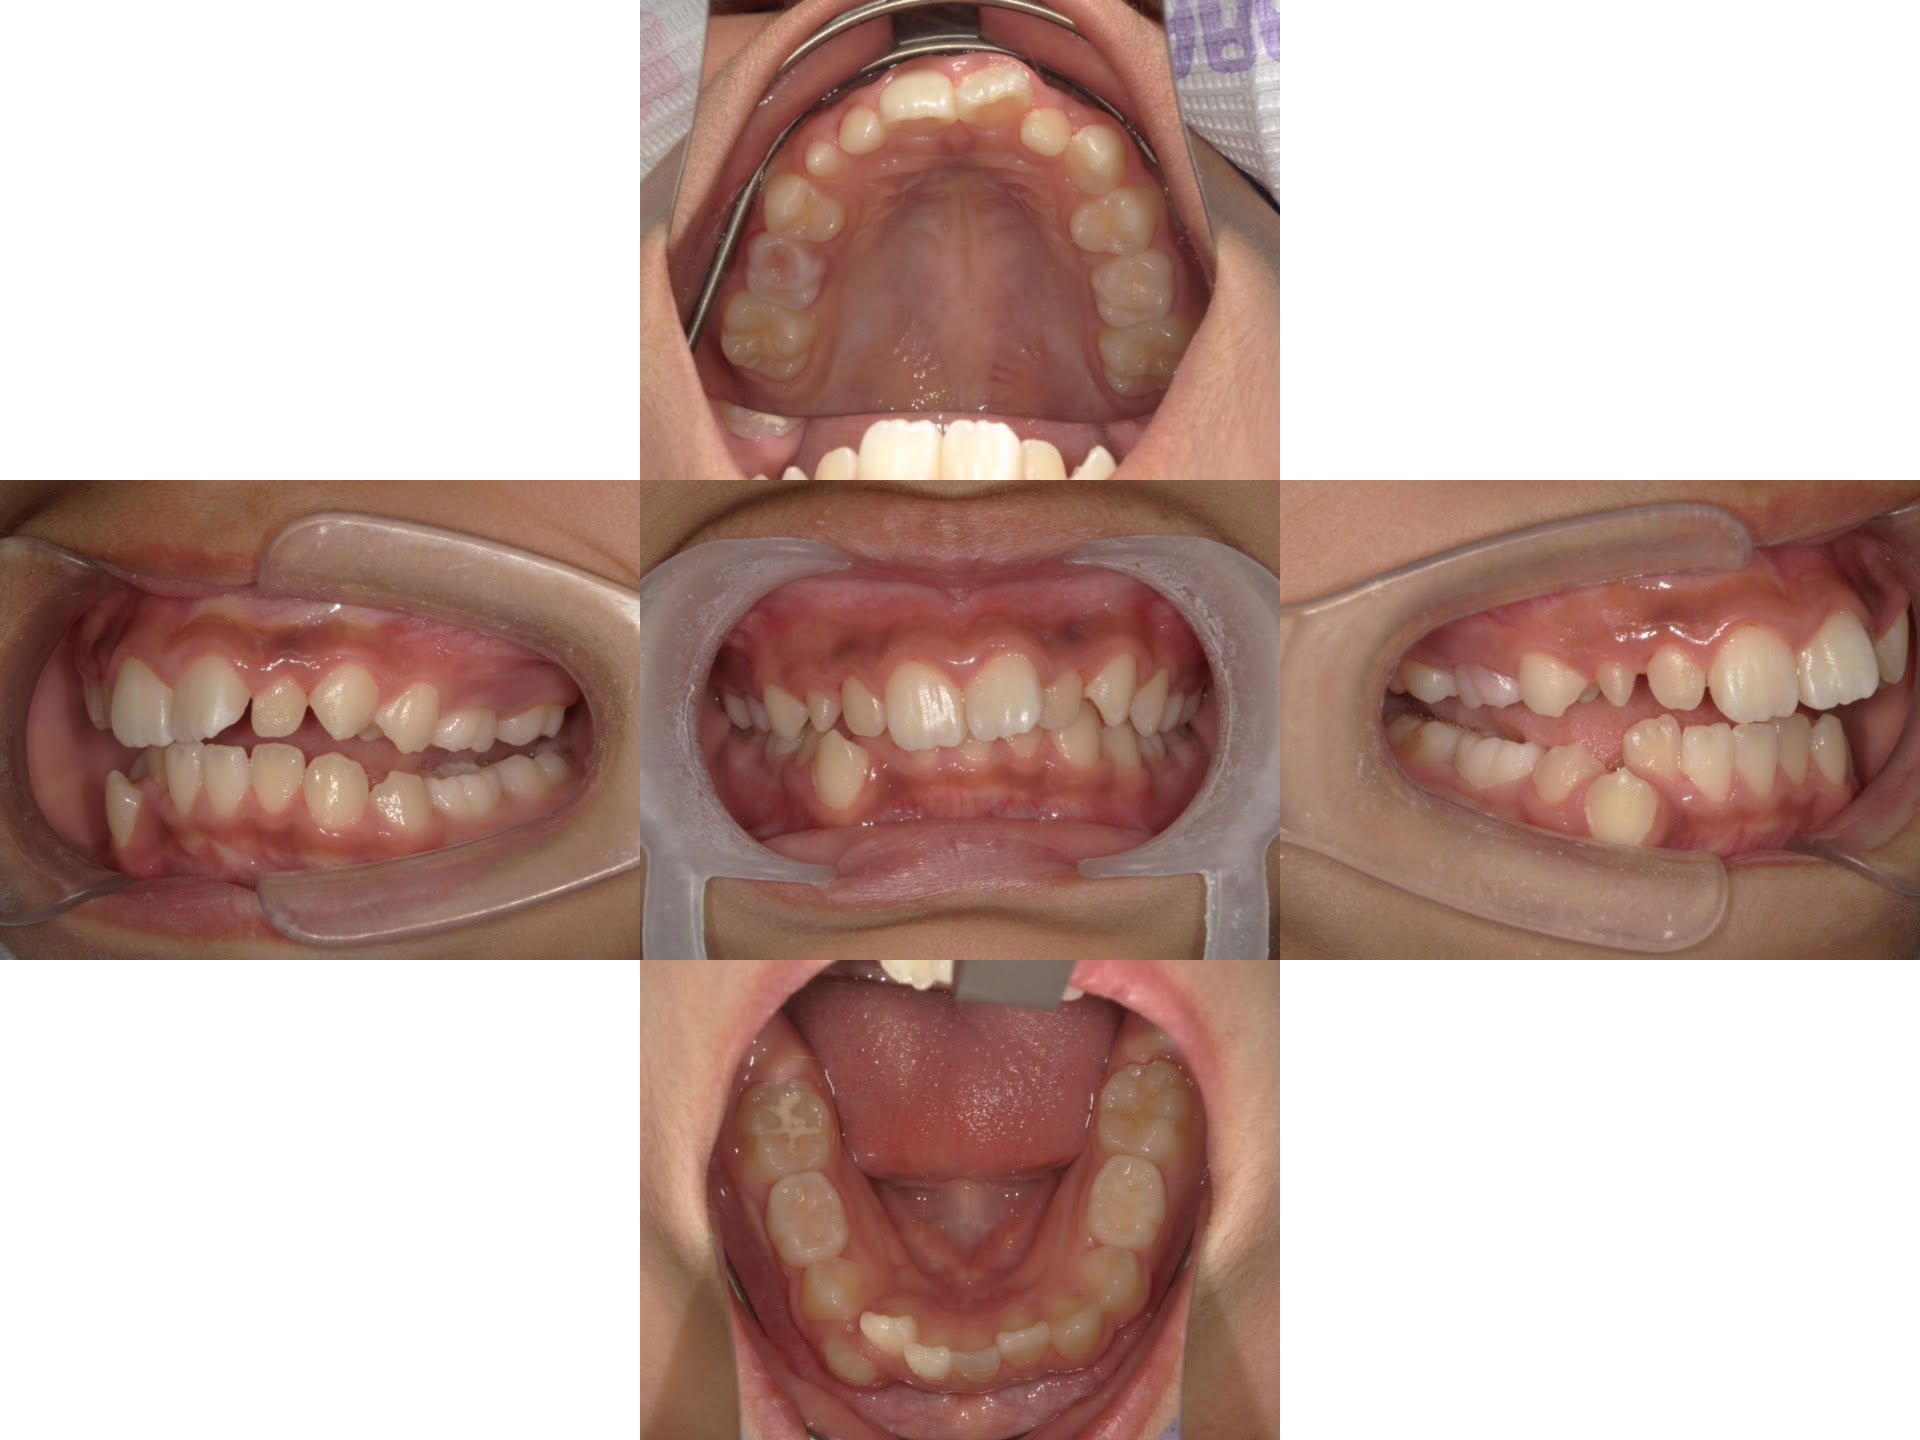

治療後

| 患者様 | 10代(小学生)女性 |

|---|---|

| 主訴 | 歯並びの乱れを改善したい |

| 治療内容 | マウスピース矯正(非抜歯) 矮小歯の右上3番にコンポジットレジンを貼り付ける治療を実施 |

| 治療期間 | 1年9ヶ月 |

| 通院回数 | 26回 |

| 治療費 | 小児矯正診断料 3万3千円(税込) マウスピース矯正 44万円(税込) 毎月の管理・処置料金 4400円×20回=88000円(税込) 合計64万9000円 |

| リスク | 矯正のマウスピースによる不快感や痛みがある場合があります 歯の動きには個人差があり、当初予定されていた治療期間より時間がかかる場合があります |